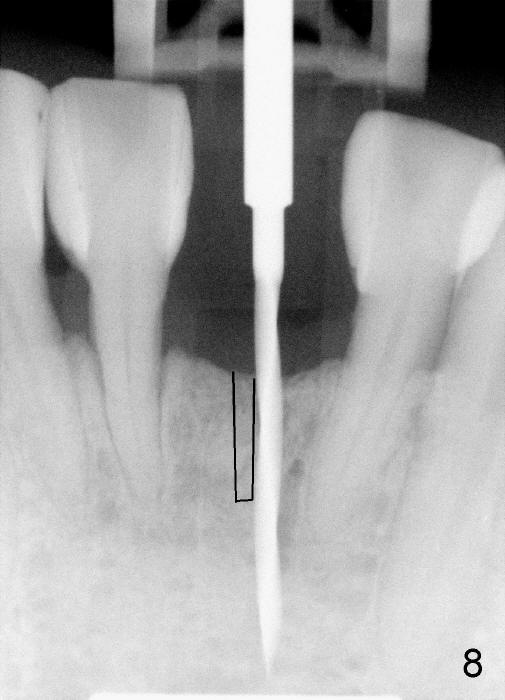

To place the implant correctly, the preop PA should be studied carefully to find the divergence of the roots of the neighboring teeth (Fig.1).  The depth of the initial osteotomy should be shorter, for example, 11 mm instead of 14 mm.  Once the trajectory is found to be corrected, an incision should be made; the osteotomy is to be overcorrected with Lindermann bur (Fig.8 black); the whole osteotomy is changed with proper angulation (Fig.9 arrows).